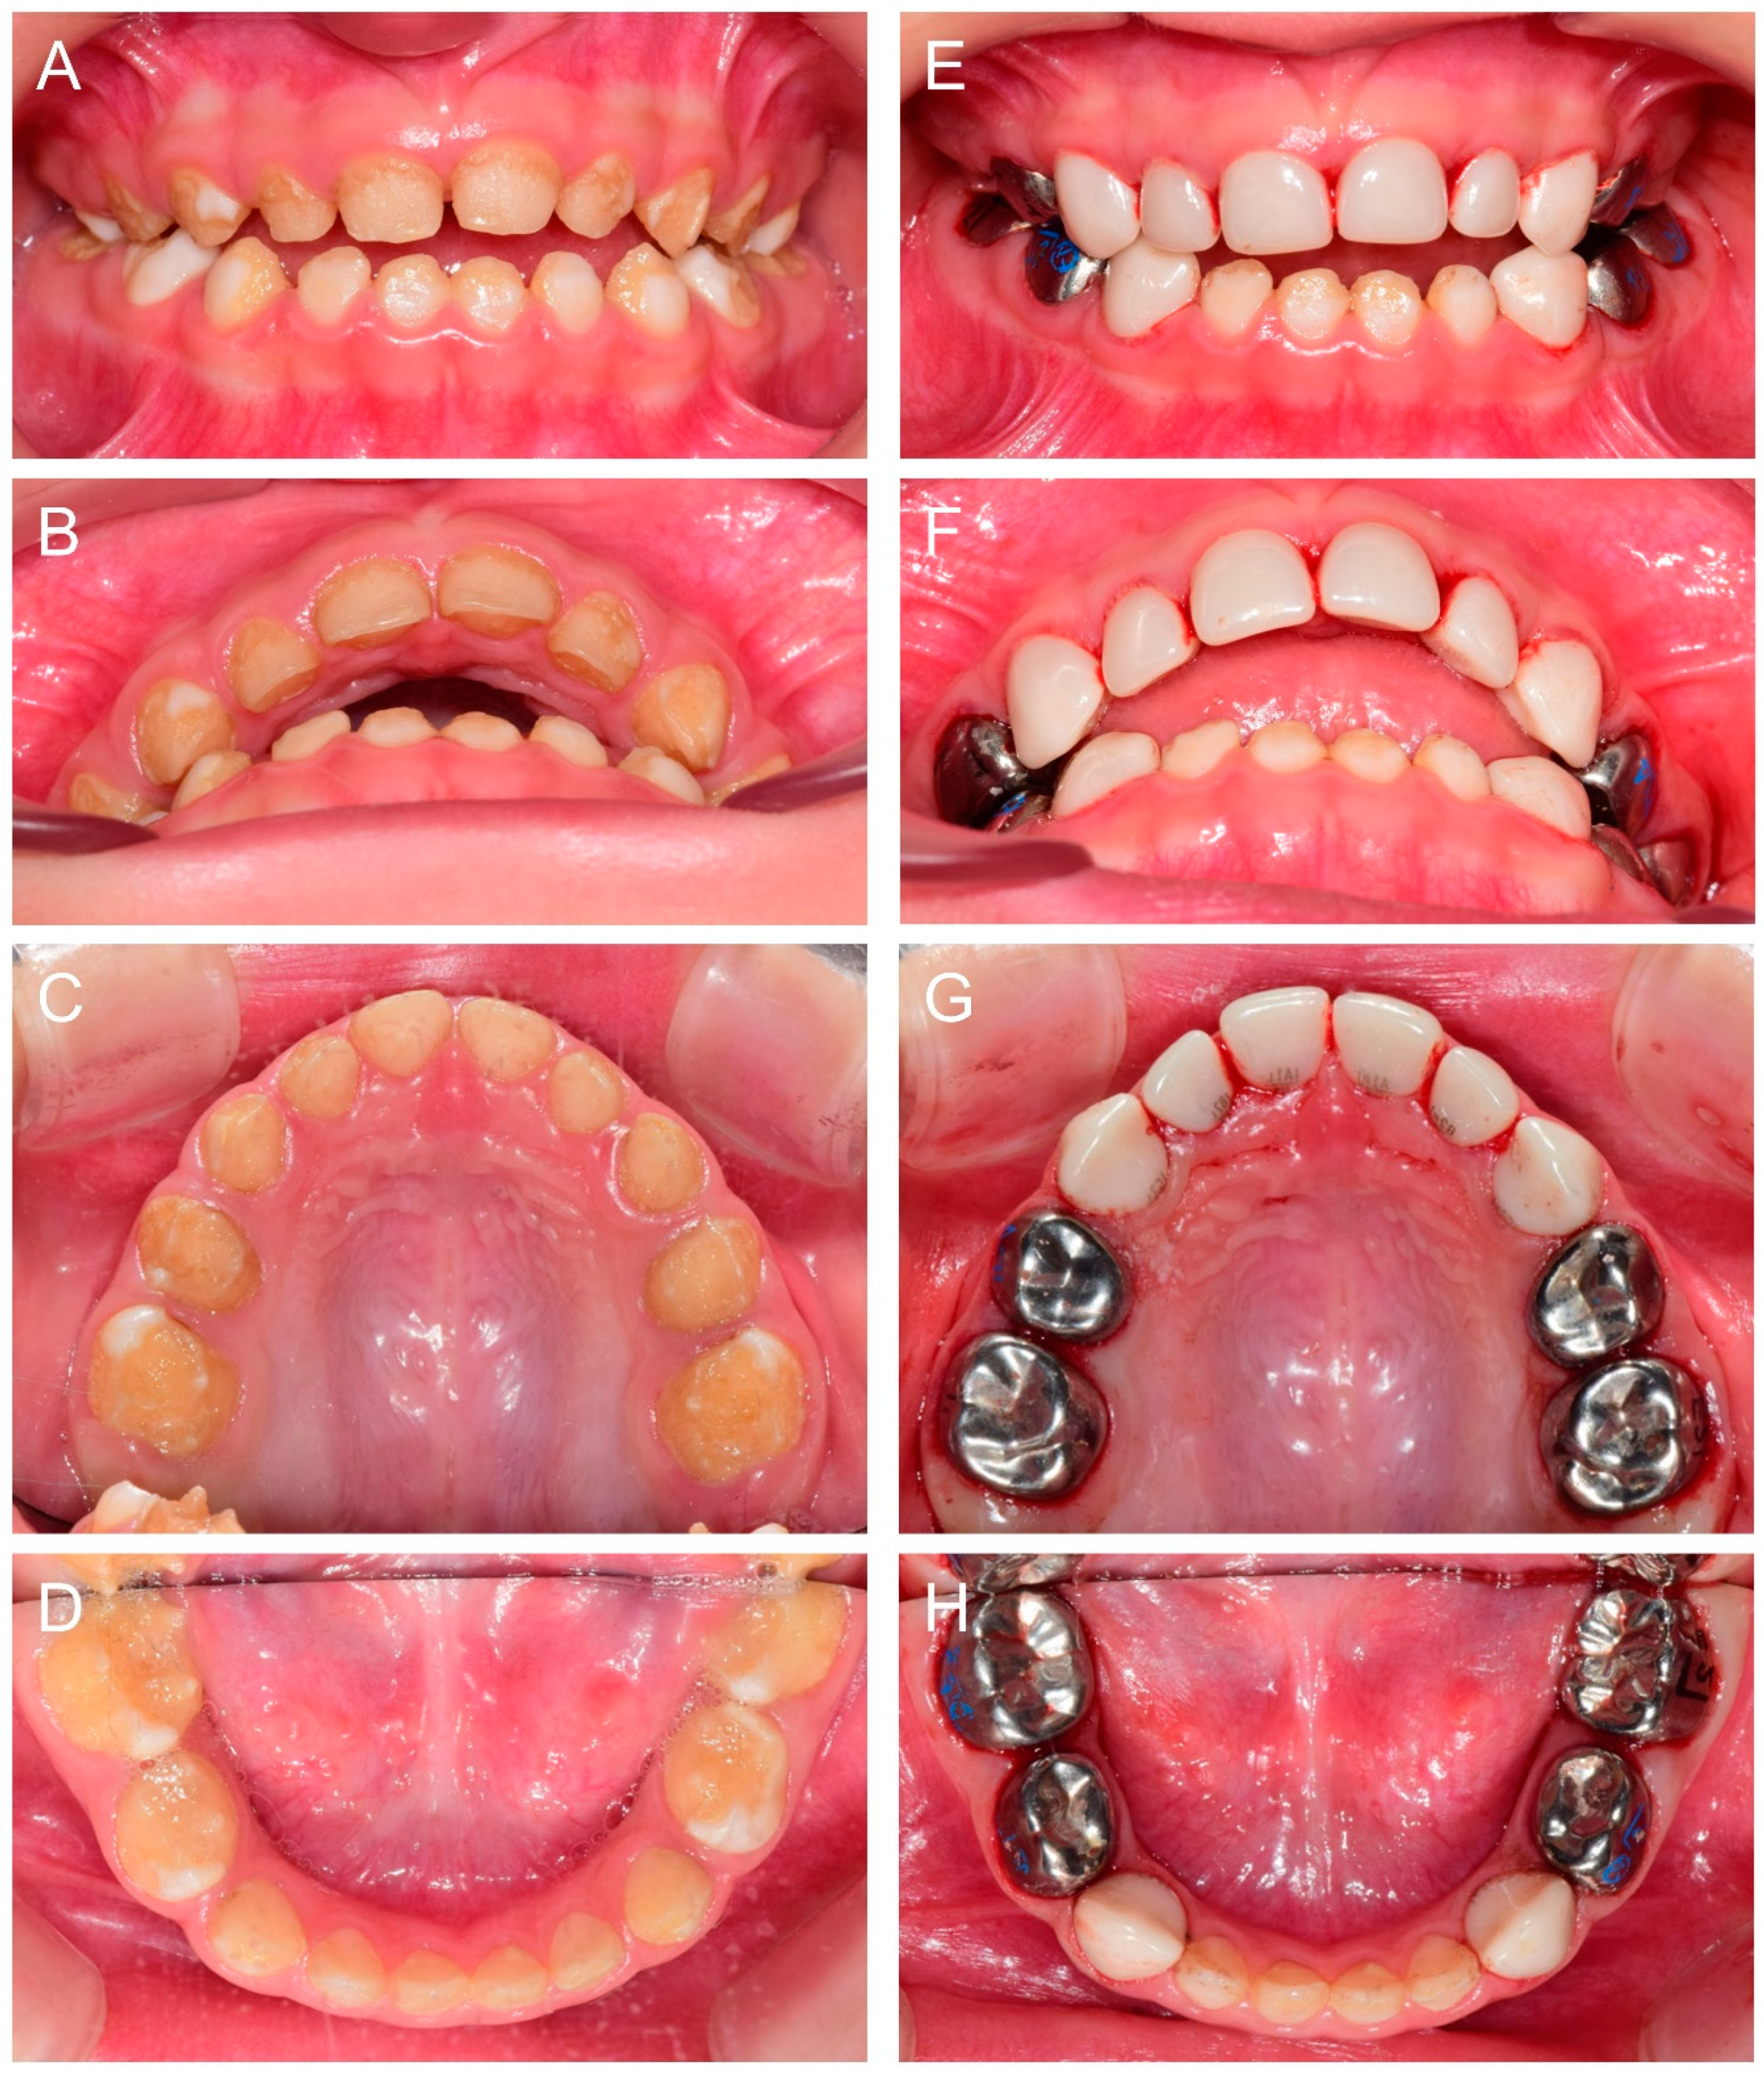

At 2Y9M, full-mouth restoration was performed under outpatient GA (Figure 2). Deciduous molars were treated with stainless steel crowns. Deciduous canines and maxillary anterior teeth were treated with zirconia crowns. Deciduous mandibular anterior teeth were left untreated. At the 3Y11M follow-up (Figure 3), good oral health was maintained, and the anterior open bite was spontaneously corrected with the discontinuance of the finger sucking habit.

Figure 3.

Clinical photos and panoramic radiograph of the proband at age 3 years 11 months. (A–E) Oral health and restorations were well maintained. Anterior open bite was spontaneously corrected with the discontinuance of the finger sucking habit. (F) Panoramic radiograph showed hypocalcified enamel in the developing permanent teeth.